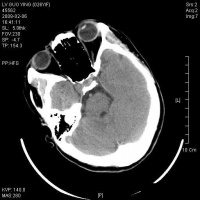

脑干损伤CT图

癫痫发作,肢体运动情况,接受过何种处理。伤前有无酗酒、精神失常、癫痫、高血压心脏病、脑中风等。